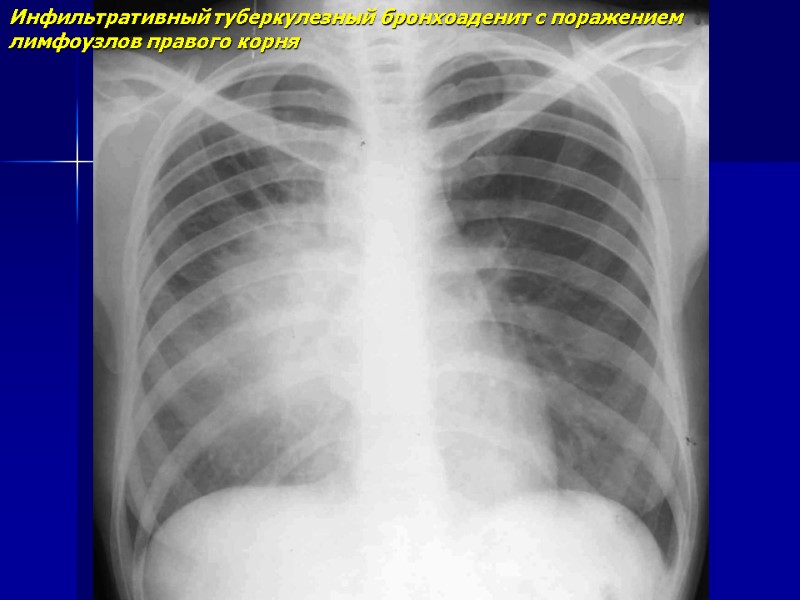

Инфильтративный туберкулезный бронхоаденит с поражением лимфоузлов правого корня

Инфильтративный туберкулезный бронхоаденит с поражением лимфоузлов правого корня